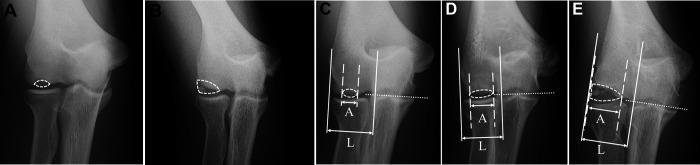

This study retrospectively evaluated adolescent baseball players with unstable elbow OCD who underwent surgery between January 2000 and February 2020. Patients were excluded if they had osteoarthritis of the elbow. A total of 139 elbows were included in this study (138 male and 1 female athlete; mean ± SD age, 13.6 ± 1.5 years). The patients were first divided into 2 groups based on OCD location: a central lesion group (72 elbows) and a lateral group (67 elbows). Next, patients were divided according to OCD size into a localized group (56 elbows) and a widespread group (83 elbows). Finally, OCD lesions that were both lateral and widespread were defined as lateral-widespread (60 elbows), resulting in 5 groups. ME apophyseal fragmentation and elongation were evaluated and defined as ME lesions. We then compared the relationship between OCD and ME lesions.

方法